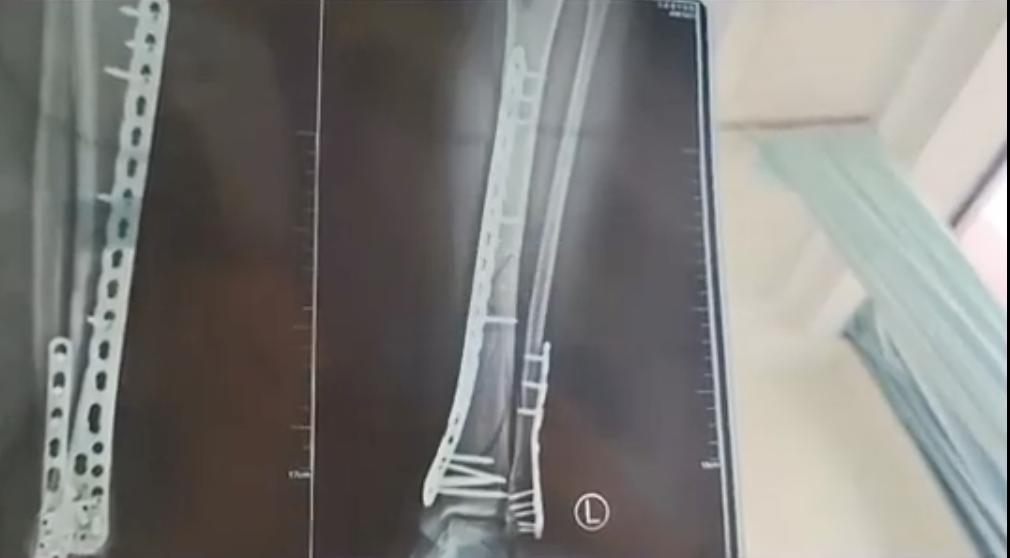

致使左腿

粉碎性骨折

武女士表示目前她已做完手术在家休养

完全康复可能需要3个月